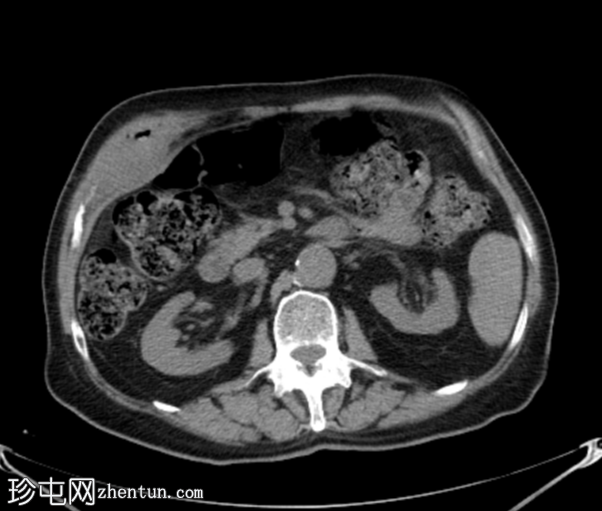

2.png

轴位增强扫描

动脉期

胆囊底部可见一枚较大的(3厘米)高密度结石,胆囊壁增厚并强化,主要位于胆囊底部。胆囊壁可见一小穿孔,感染扩散至胆囊外,并在肝下区可见气体腔。感染进一步扩散至腹壁肌肉,腹壁肌肉内可见脓肿,边缘强化明显,囊性坏死中心,腔内可见气体腔。十二指肠第一段与炎症胆囊粘连。

检查结果提示急性胆囊炎合并腹壁脓肿。